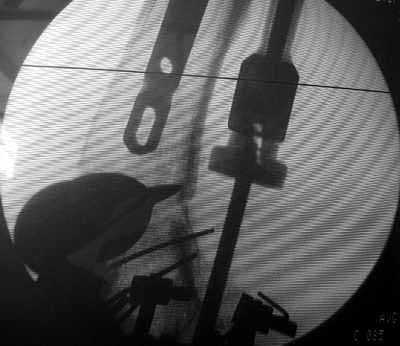

Well, finally i still performed antegrade nailing. After the distractor was applied, reduction of the recent fracture was obtained "automagically".

But the previous fracture resulted with some posterior displacment of the distal part, so antegrade nail would pass anteriorly, and retrograde nail, even a short one, would have penetrated anterior cortex proximally to the fracture. So perQ osteotomy was necessary to add some mobility at the level, and after that the nail was easily inserted to the distal fragment. The nail is solid, 13 mm, locking screws 6 mm. Locked statically.